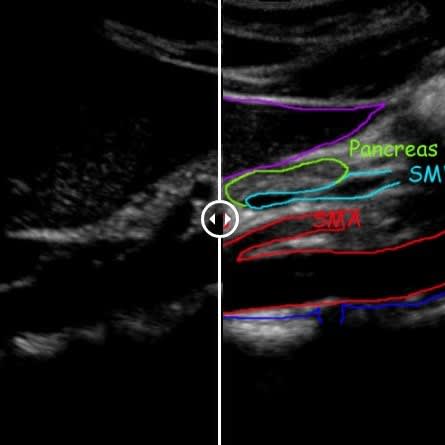

Vascular Services

Allow our dedicated team to put you at ease, while we boast about having top of the range equipment and overqualified staff. Outstanding patient care comes as standard here at NumiScan North London.